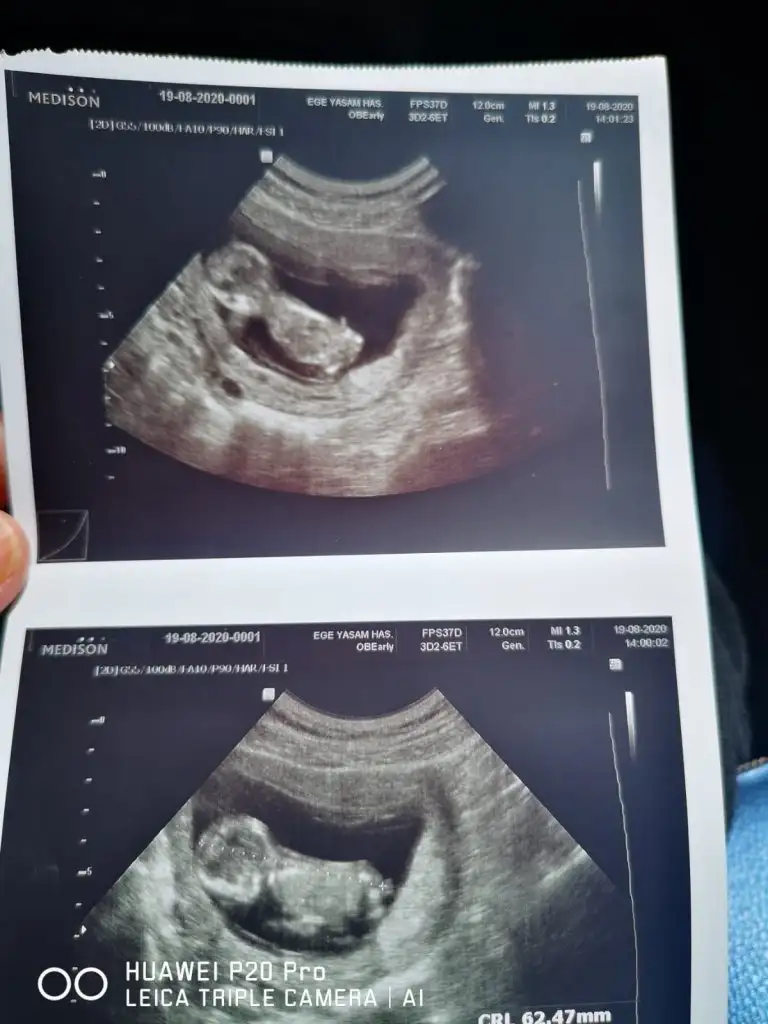

Emin değilim sanki kız ama emin değilim varsa başka USG paylaşın 11 12 13 haftalar olmalıİkra Meyra tahminin var mı.doktor göremedi.ters durmuş hareket etmedi hiçEki Görüntüle 2678263

Emin değilim sanki kız ama emin değilim varsa başka USG paylaşın 11 12 13 haftalar olmalı

Banada paylaşın USG ler 11 12 13 haftalar olmalı